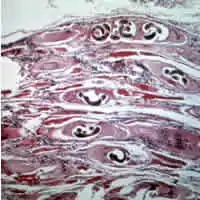

| Trichinella larvae in pressed bear meat, partially digested with pepsin. The classic coil shape is visible. | |